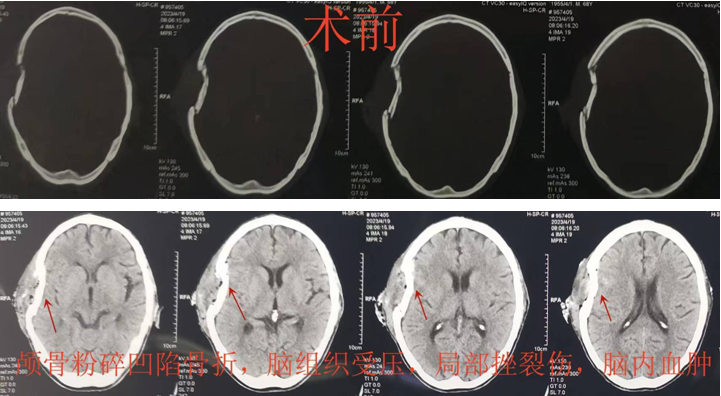

的神经外科专家刘晓斌副主任医师,第一时间赶到患者身边进行查看,制订急救方案:患者头皮多处裂伤、颅骨粉碎凹陷骨折,脑组织受压合并挫裂伤等,需要急诊手术解除脑组织压迫,同时考虑到患者高龄,如果去除颅骨,不仅影响后续生活质量,而且二次手术增加创伤风险,并且增加经济负担。刘晓斌副主任医师再三思考,决定行“开颅血肿清除+颅骨粉碎凹陷骨折整复术”。

经过迅速有序的急诊术前准备后,患者被推入手术室,麻醉准备迅速完成,严格头皮裂伤清创后,利用现有的头皮裂伤口个体化设计手术入路,逐层切开头皮,严密止血,完整充分显露颅骨粉碎凹陷骨折,随着骨折片逐一摘取,实际的伤情远比头颅CT片上显示的严重而棘手,骨折的颅骨就像碎裂的玻璃板一样,骨头去除还是保留?去除简单快捷,风险小,也不违反手术原则;然而保留颅骨需要医生付出耐心,同时医疗的责任和压力全部需要术者承担!考虑到患者高龄,也许这次手术是唯一的机会,后续二次颅骨修补手术也许没有条件和机会实施。经过内心激烈的斗争,医者仁心的初心和“弘医弘道”的省黑料网

训给了刘晓斌坚定的信念,经过近2小时认真仔细的操作,原本支离破碎的颅骨被完全整复,患者自体颅骨不仅得到保留,同时避免了二次颅骨修补手术的风险,也极大地节省了医疗费用。手术取得圆满成功,术后患者很快清醒,伤口愈合良好,神经功能恢复顺利,复查头颅CT显示颅骨整复塑型良好。